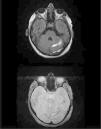

El día 11.° del ingreso se realiza ventana de sedación, presentado la paciente apertura ocular espontánea con disfasia motora leve y hemiparesia derecha de predominio braquial. En una TAC craneal urgente con contraste se descubren defectos de repleción en los senos venosos sagital superior, recto, transverso y sigmoide izquierdos, en relación a la TVC, e infartos en región frontotemporal y hemisferio cerebeloso izquierdos con áreas hemorrágicas. Se inicia tratamiento con heparina de bajo peso molecular y se completa estudio con RM craneal y angio-RM venosa cerebral que confirma el diagnóstico (figs. 1 y 2). En el estudio de hipercoagulabilidad destaca una determinación de anticoagulante lúpico positiva. Dada la presencia de componente hemorrágico en el infarto cerebral y la evidencia disponible8, se decidió continuar tratamiento anticoagulante con dabigatrán. En las semanas posteriores en planta presenta una evolución lentamente progresiva con estabilidad respiratoria, iniciándose tratamiento rehabilitador con tendencia a la mejoría de la hemiparesia y recanalización parcial de la TVC con control de la RM a los 2 meses, sin otras complicaciones.

Angio-RM cerebral que muestra trombosis venosa extensa, que afecta a senos longitudinal superior, transverso y sigmoide de ambos hemisferios (A). Control en un mes (B) con recanalización parcial del seno longitudinal superior, transverso y sigmoide izquierdos tras tratamiento con dabigatrán.